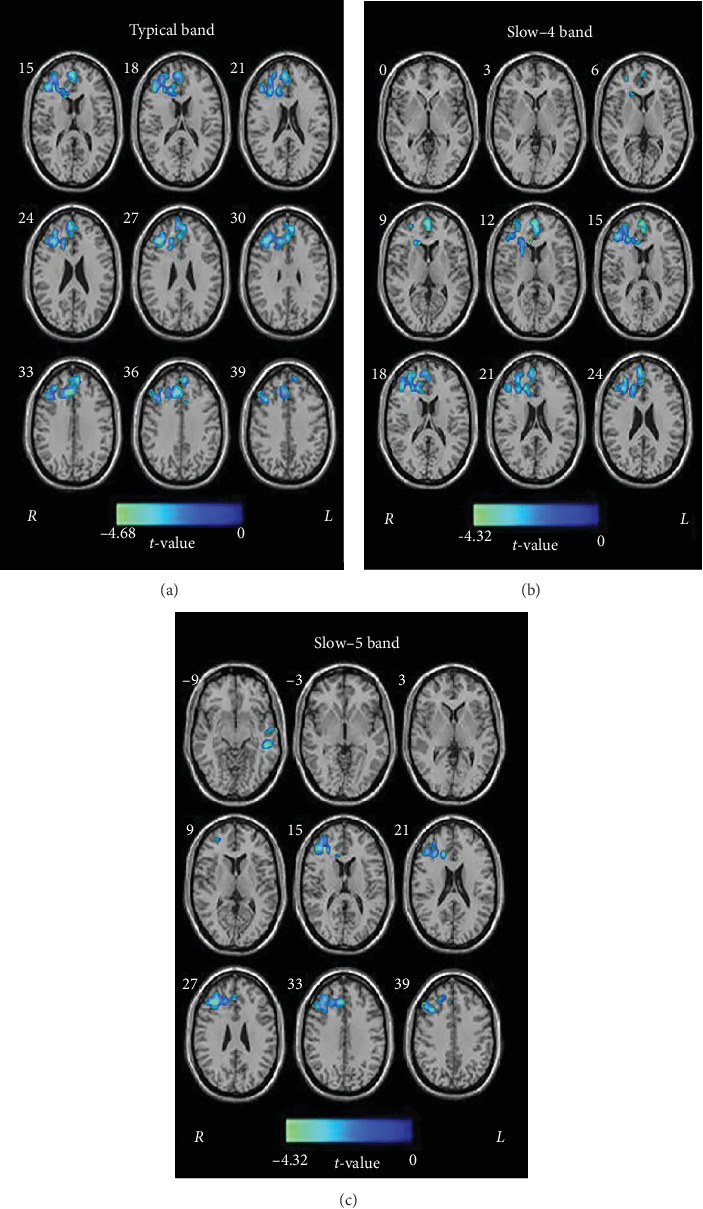

Purpose: This study aims to investigate functional abnormalities in transient ischemic attack (TIA) patients compared to healthy controls (HCs) using percent amplitude of fluctuation (PerAF) across multiple frequency bands derived from resting-state functional magnetic resonance imaging (rs-fMRI). Methods: We scanned 48 TIA patients and 41 HCs using rs-fMRI and high-resolution T1-weighted brain images. Both PerAF and modified PerAF (mPerAF) were utilized for comparative analysis across the typical frequency band (0.01-0.08 Hz) and two subfrequency bands: slow-4 (0.027-0.073 Hz) and slow-5 (0.01-0.027 Hz). Two-sample t-tests were conducted to assess group differences, with multiple comparisons correction using Gaussian random field (GRF) methods. Results: Compared to HCs, TIA patients exhibited significantly lower PerAF in the right inferior frontal triangular gyrus in both the typical and slow-5 bands. Additionally, reductions were observed in the right superior frontal medial gyrus in the slow-4 band and the left middle temporal gyrus in the slow-5 band. No significant differences were observed in mPerAF. Conclusion: These findings suggest a significant impact of TIA on multiple brain regions, with frequency-specific alterations in PerAF, providing novel insights into the underlying mechanisms of TIA.